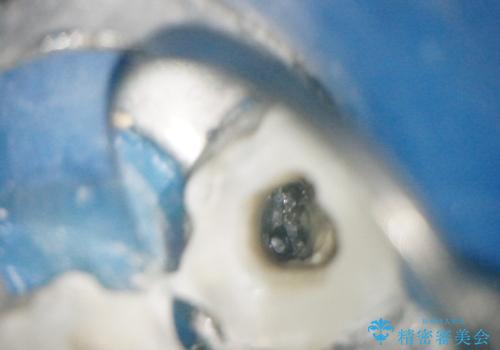

【外部吸収】根管治療、外科治療からのオールセラミッククラウン

根管治療後、外部吸収を認めたため歯周外科を行ない歯冠修復を行なっております。

根管治療後には速やかに歯冠修復が必要です。